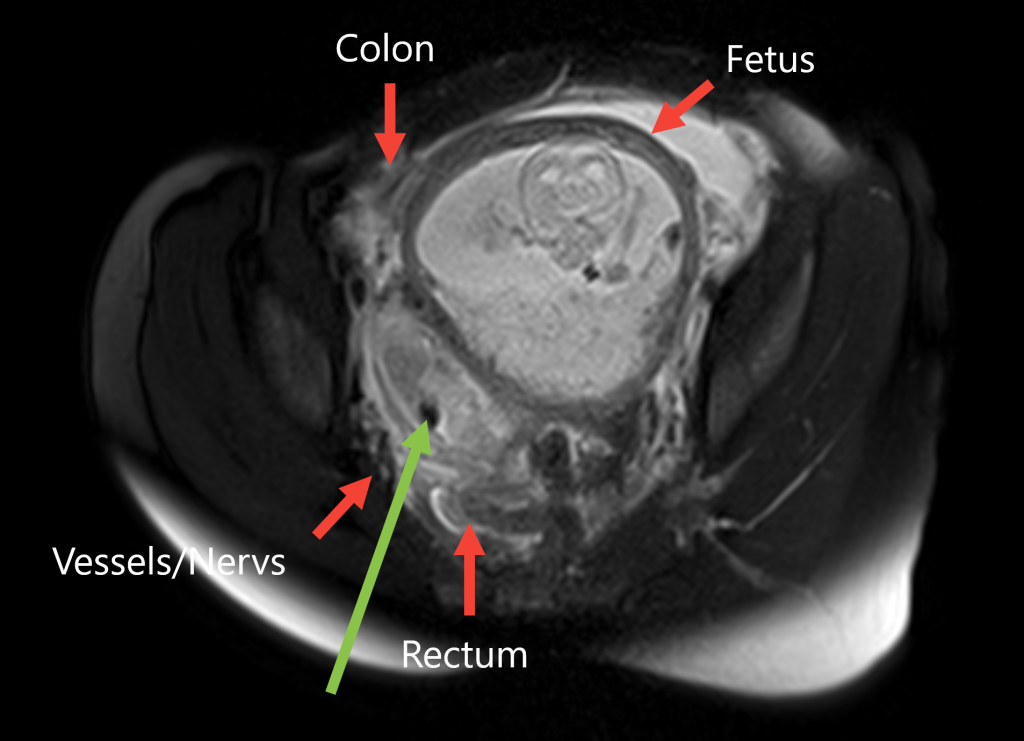

MR-guided Pain Management

The piriformis muscle is a gluteal muscle that, due to causes such as muscle tension or shortening, can exert pressure on the adjacent sciatic nerve. This results in a compression syndrome, which presents with typical sciatica symptoms, including radiating pain into the buttock and leg.

In severe, chronic cases, MRI-guided injection of botulinum toxin A (Botox®) into the piriformis muscle is a minimally invasive, image-guided treatment option [4][5]. The neurotoxin blocks signal transmission from nerves to the muscle, leading to temporary denervation and weakening of the muscle. Pain relief is achieved through reduced muscle tone, and the decreased muscle volume also relieves pressure on the neighboring sciatic nerve, resolving the compression.

A key advantage of MRI-guided injection is that both the needle and the muscle can be visualized, allowing very precise delivery of botulinum toxin into the affected muscle. This significantly improves safety and effectiveness. In addition, the painful sciatic nerve can be temporarily anesthetized along its course below the piriformis muscle (in the infrapiriform foramen) by injecting long-acting local anesthetics and corticosteroids. This is often helpful in breaking acute pain cycles.

At the Institute of Diagnostic and Interventional Radiology, this procedure is used both clinically and in research to further refine and evaluate the technique. We work closely with the Department of Rehabilitation Medicine at Hannover Medical School (MHH), which thoroughly evaluates patients and excludes other causes of symptoms.